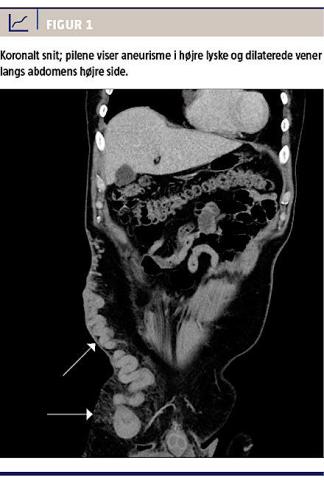

Objektivt fandt man fra højre lyske en stor subkutan udfyldning, der strakte sig 10 cm lateralt og kranialt og gav ømhed ved palpation (Figur 1). En biokemisk undersøgelse viste en normal laktatkoncentration og forhøjet D-dimerkoncentration på 0,45 mg/l, men ellers normale forhold. Patienten fik foretaget akut computertomografi (CT) af abdomen, hvor man beskrev dilateret vene i højre fossa og mistanke om trombe i venen eller inkarcereret lyskebrok. Unersøgelsen blev primært tolket radiologisk som et lyskebrok på 5 × 3 cm, og der var mistanke om strangulation (Figur 1). Kirurgisk blev det efterfølgende vurderet, at der ikke var sammenhæng mellem anamnesen, de objektive fund og tolkningen af CT’en. Karkirurgerne vurderede efter konference, at patienten havde VCA infrarenalt og ikke hernie. Patienten fik foretaget en ultralydskanning, som viste DVT i et aneurisme i højre lyske, hvilket også efterfølgende kunne ses på CT. Patienten blev sat i relevant antikoagulansbehandling. Trods dette fik han et døgn senere trykken i brystet ved dyb inspiration, men uden dyspnø. En elektrokardiografi gav mistanke om lateralt inferiort infarkt, og troponinkoncentrationen steg fra 2,83 til 5,50 mikrogram/l. D-dimerkoncentrationen faldt til 0,17 mg/l. Mistanke om akut myokardieinfarkt og lungeemboli udløste en spiral-CT, ekkokardiografi og koronarangiografi, som viste normale forhold. Ifølge den kardiologiske bagvagt var der tale om ST-segmentelevationsmyokardieinfarkt på baggrund af paradoks emboli fra DVT i lysken. Ved udskrivelsen blev der anbefalet opfølgende transøsofageal ekkokardiografi på grund af mistanke om persisterende foramen ovale eller speciel venøs anatomi. Patienten rejste imidlertid til Sverige, og yderligere information om det videre forløb foreligger ikke.